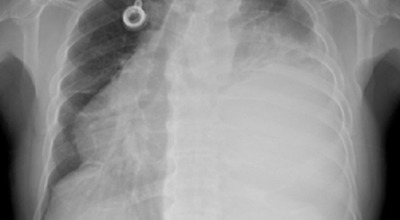

폐암 초기 증상 중 하나로 호흡곤란이 나타날 수 있습니다. 폐암 환자의 약 50%가 숨이 차다고 느낀다고 알려져 있어요. 이는 암 덩어리가 커져 숨이 가빠지는 경우도 있지만, 폐암으로 인한 폐 허탈, 상기도 폐색, 흉막 삼출 등이 호흡곤란을 일으키기도 합니다. 평소와 달리 숨이 차고, 숨을 들이쉬거나 내쉴 때 쌕쌕거리는 소리가 난다면 폐암 초기 증상을 의심해 볼 필요가 있습니다.

폐암 초기 증상으로는 혈담이 있습니다. 혈담은 쉽게 말해 가래에 피가 섞여 나오는 경우를 뜻합니다. 폐암이 폐 중앙부 기관지 근처에 위치할 경우 나타나는 혈담은 폐암 환자의 25% 이상이 경험하는 증상입니다. 만약 기침할 때 심한 가래나 혈담이 섞여 나온다면 즉시 병원을 방문하시길 권합니다.